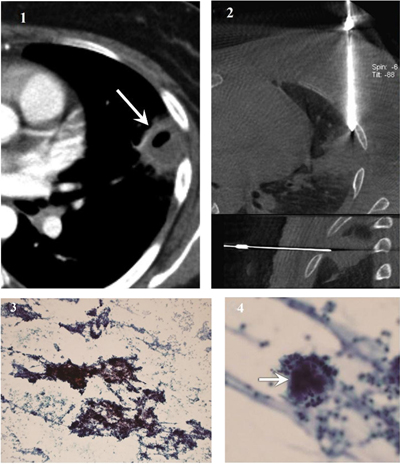

Figure 4

Actinomycosis diagnosed using samples from fine needle aspiration. (1) CT image shows a subpleural cavitary consolidation in the left upper lobe (arrow). (2) Cone-beam CT-guided CT images (upper, axial; lower, sagittal) show coaxial guide-needle placement to the target lesion. (3) Photomicrograph of cytological smear (Papanicolaou stain, original magnification × 100) shows clumps of basophilic bacterial colonies admixed with neutrophilic suppurative inflammatory infiltrates (4) Magnified photomicrograph of cytological smear (Papanicolaou stain, original magnification × 400) shows sulfur granules with dense center (arrow) surrounded by delicate filaments. The left upper lobe lesion disappeared after appropriate antibiotic therapy.